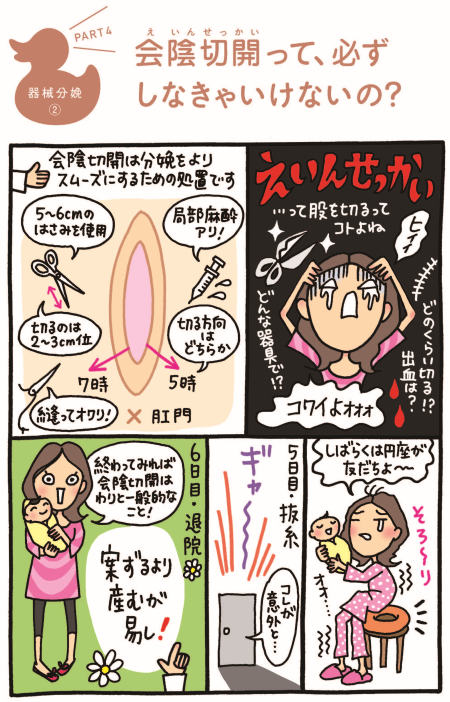

会陰切開について東京・世田谷での出産・分娩なら国立成育医療研究センター 産科。

会陰切開 をするタイミングは?痛みはある?切らない人もいる?会陰切開の不安と疑問に産婦人科医がお答えBaby-mo ベビモ。

会陰切開、吸引・鉗子分娩 出産のときの大切な医療処置たまひよ。

会陰切開 をするタイミングは?痛みはある?切らない人もいる?会陰切開の不安と疑問に産婦人科医がお答えBaby-mo ベビモ。

会陰切開、吸引・鉗子分娩 出産のときの大切な医療処置たまひよ。